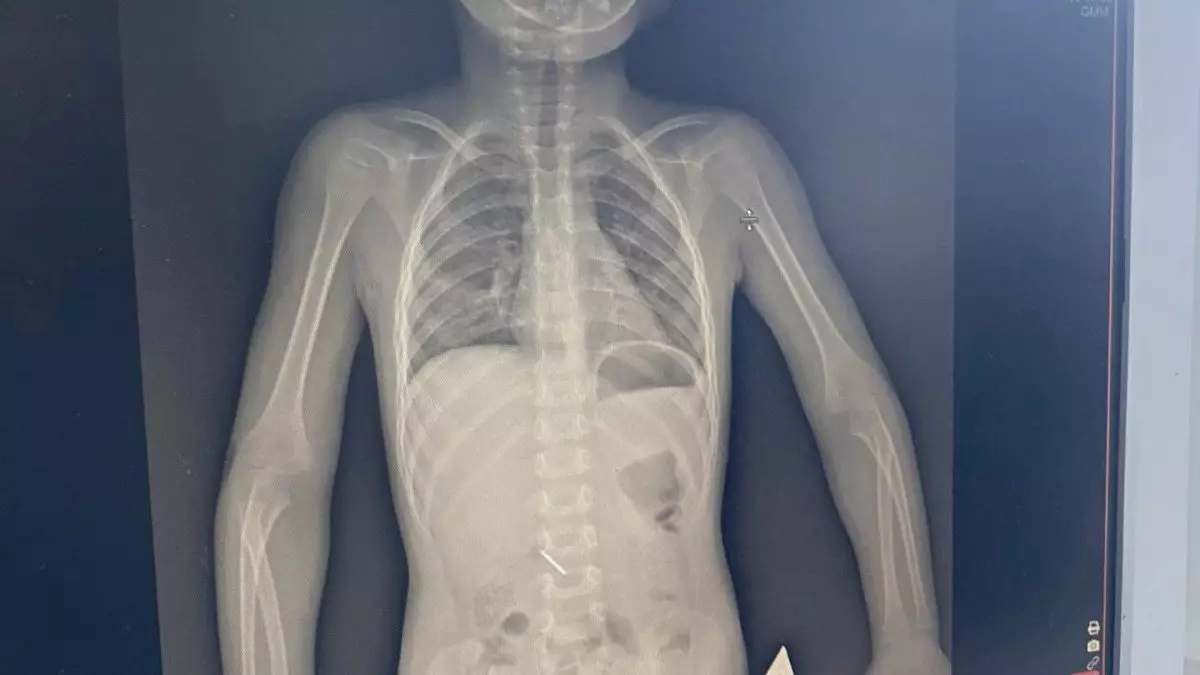

«Кешірім де сұрамады»: Көкшетауда бүлдіршін тісін емдетемін деп оқыс жағдайға ұшырады

26 ақпандағы жағдай бойынша, бөгде зат әлі табиғи жолмен шықпаған.